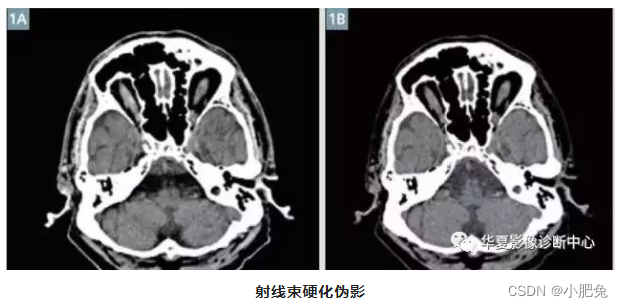

三、放射束硬化伪影

放射线束硬化是指X线透过物体后射线束平均能的增加。 当被扫描物体的尺寸由小变大时, 通过物体的低能射线被吸收, 平均射线能由左边移向右边(高能端),使某些结构的CT值改变并产生伪影。 此外, 射线束硬化也与射线通过的路径长短有关。 在一个圆形物体中(人体横断面形状通常可被看作是一个圆形物体) , 射线通过路径剖面图上, 中心部分的路径要长于边缘部分, 两者通过物体后都产生射线的硬化, 而路径长的射线硬化要大于路径短的射线。 射线束硬化使X线光子吸收不均衡, 相应产生部分高信号, 如果这种非线性哀减不作补偿, 会产生条状或环状伪影。

射线硬化伪影: Hounsfield bar表现为一条黑暗的条状伪影,出现于颅底颞骨水平,遮盖了脑干中间部分的图像(图1A)。图1B显示的是与图1A相同层面,但对射线硬化伪影进行了校正。

射线束硬化伪影抑制的方法:在X线源与人体之间加装滤过装置,使X线能虽分布均匀,射线束硬化效应得到补偿,从而消除伪影。技术人员在设置扫描计划时,应尽可能避开骨性结构,减小硬化效应可能导致的伪影。另外,调节窗宽窗位也能使射线束硬化伪影改善 。